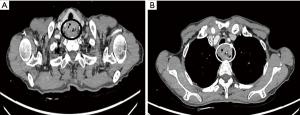

After the informed consent was obtained from the patient and her family, an individualized therapeutic strategy was designed. Total laryngopharyngoesophagectomy combined with low AMT was performed under general anesthesia. The esophagus was mobilized under a thoracoscope, and the tubular stomach was created laparoscopically. After a Y-shaped incision was made in the cervical thorax, the anterior cervical muscles were dissected, and the thyroid gland was preserved. Afterward, the cervical systemic lymph node dissection was done. After total laryngectomy, the trachea was resected about 3 cm above the carina, and the trachea was intubated intraoperatively for ventilation. The sternoclavicular joint, the sternal stalk and the medial portions of rib cartilage were all removed, but the clavicle was preserved. Then, the tubular stomach was uplifted to the neck via the posterior mediastinal route for manual anastomosis. Double S-shaped pectoralis major musculocutaneous flap were harvested at the upper edge of the sternal stump for repairing the tracheal stump (Figure 4). A low AMT was performed on the chest. During this process, the trachea traveled inferior to the left innominate vein and right to the brachiocephalic trunk. The greater omentum was preserved for filling the anterior mediastinal area during the tubular stomach uplifting, while the bilateral sternocleidomastoid muscles were also used to fill the anterior mediastinal area. Thus, the tubular stomach was isolated from the trachea (Figure 5). Negative pressure drainage was placed on both sides of the anastomosis, above and below the tracheostomy and under the skin for good drainage (Figure 6). A second chest CT was performed on the tenth postoperative day, showing that the tracheostomy was well healed, and the mediastinal area was well filled with no cavity (Figure 7).